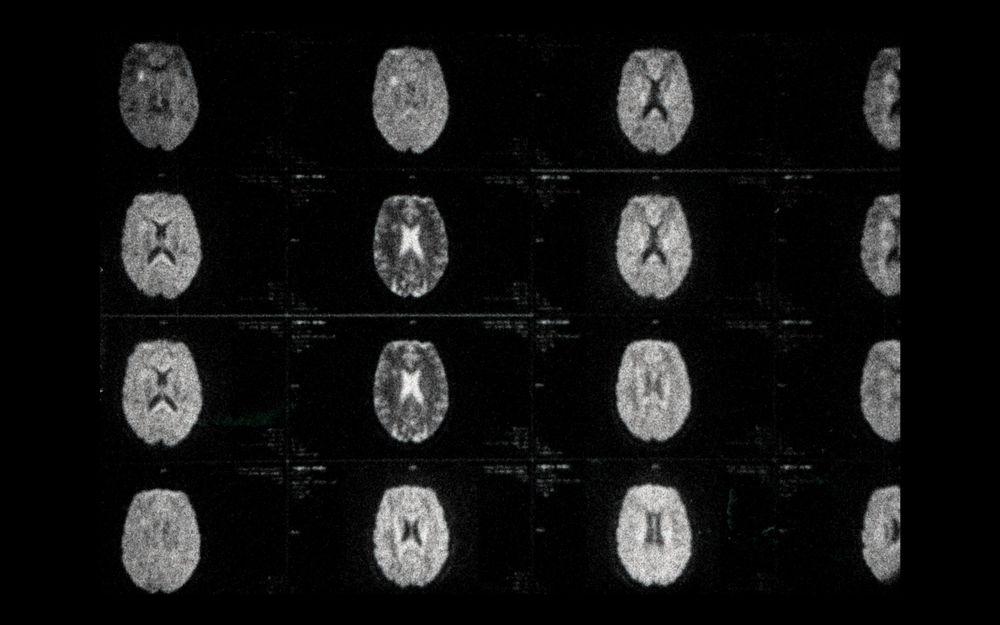

Exit Through the Cuckoo’s Nest by Nikola Ilic offers a searing critique of systemic oppression, showing mental illness as the only way out of a compulsory military service in wartime while Sarah Ballard’s Full Out delves into the transformative possibilities of the body as a site of violence, inexplicable impulses, and radical change. In the final film of the program, In My Head, Irina Tempea plunges the audience into the fragmented landscape of inner turmoil shaped by a body failing due to a tentacular disease.